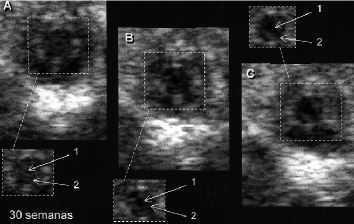

Tras obtener una respuesta normal, un segundo estímulo podía mantener más tiempo la midriasis reactiva o inducir una pupilodilatación fetal de mayor magnitud (Fig. 10). A veces, este segundo estímulo no llegaba a provocar la respuesta esperada (si el feto ya había recuperado su miosis basal), necesitando un nuevo estímulo DC para «recordar» la respuesta. Este último comportamiento refleja cierto tipo de habituación. La habituación entendida como un descenso en la respuesta después de una presentación repetida del estímulo, ha sido demostrada en los fetos humanos a estímulos sonoros desde la semana 22 de gestación(8,9) y en fetos de animales de experimentación(10,11), y se asocia con un correcto funcionamiento del sistema nervioso(12).

Figura 10. 30 semanas. Placenta previa marginal con desprendimiento parcial de placenta (2 cm) y sangrado vaginal. Fotograma A: miosis basal. Fotograma B: midriasis después de un estímulo DC. Fotograma C: la midriasis aumenta tras un segundo estímulo DC («reflejo progresivo»). 1 = Pupila. 2 = Iris.